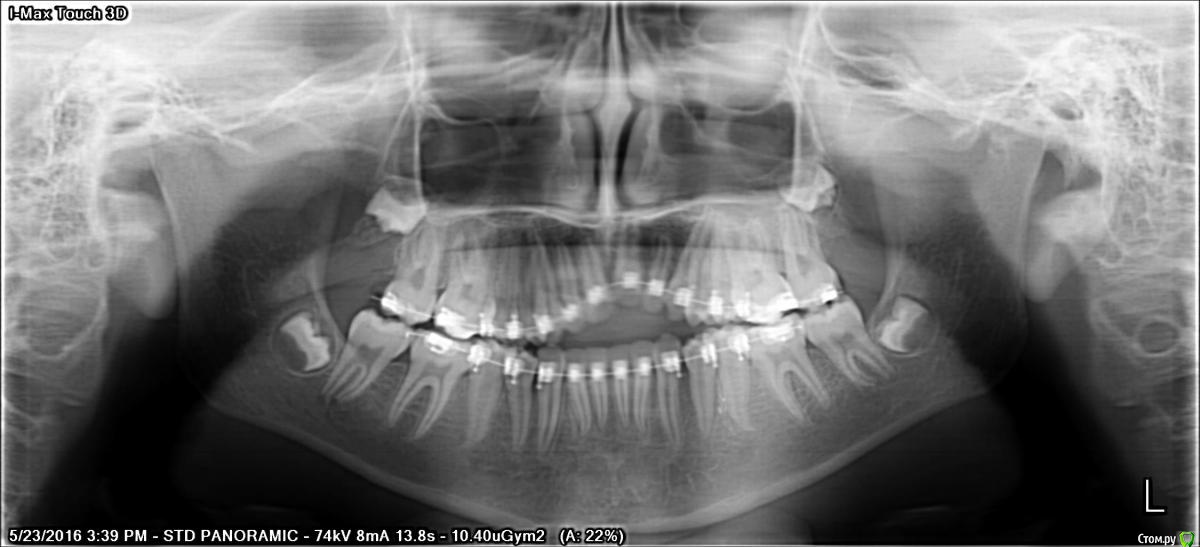

Серго Далакишвили Опубликовано 11 июня, 2016 Поделиться Опубликовано 11 июня, 2016 Здравствуйте, срочно нужен квалифицированный совет или указания.два года назад дочке поставили брикеты. ей сейчас двенадцать.место того чтоб всё исправить, всё испортили...у дочурки маленькая челюсть и врач начал расширять челюсти чтоб выиграть место.я конечно же не врач но я спросил ортодонта, может удалить четвёртый зуб появится места чтоб сдвинуть второй и третий к пятому зубу и потом спустим центральный зуб. короче конечно же меня некто не послушал и она(ортодонт) всё сделала по своему. итог. вместо того чтоб спустит один зуб подняли на верх остальные и не просто поднялись а очень....начала врач винить этот один зуб якобы это всё анкилоз.честно говоря врач в растерянности и когда я увидел её таким решил проконсультироваться у других врачей тоже.с начало сняли КТ и тут появляется самое плохое фактический кость разрушено на нескольких зубов верхней челюсти.а на нижней челюсти передняя шестёрка на столько наклонили в перёд что почти держатся на кончиках и нижней левой шестёрки виден корень.врачи посоветовали снят. брикеты дать восстановится костной ткани.люди добрые посоветуйте что делать, боюсь что если долнейшие действия будут не правильными дочка потеряет одного зуба остальные зубы.прилагаю панорамные снимки до и после, и ссылку на КТ можно скачать через www.dropbox.com https://www.dropbox.com/s/l7s5zqa777hsr70/Romexis.exe?dl=0 Ссылка на комментарий